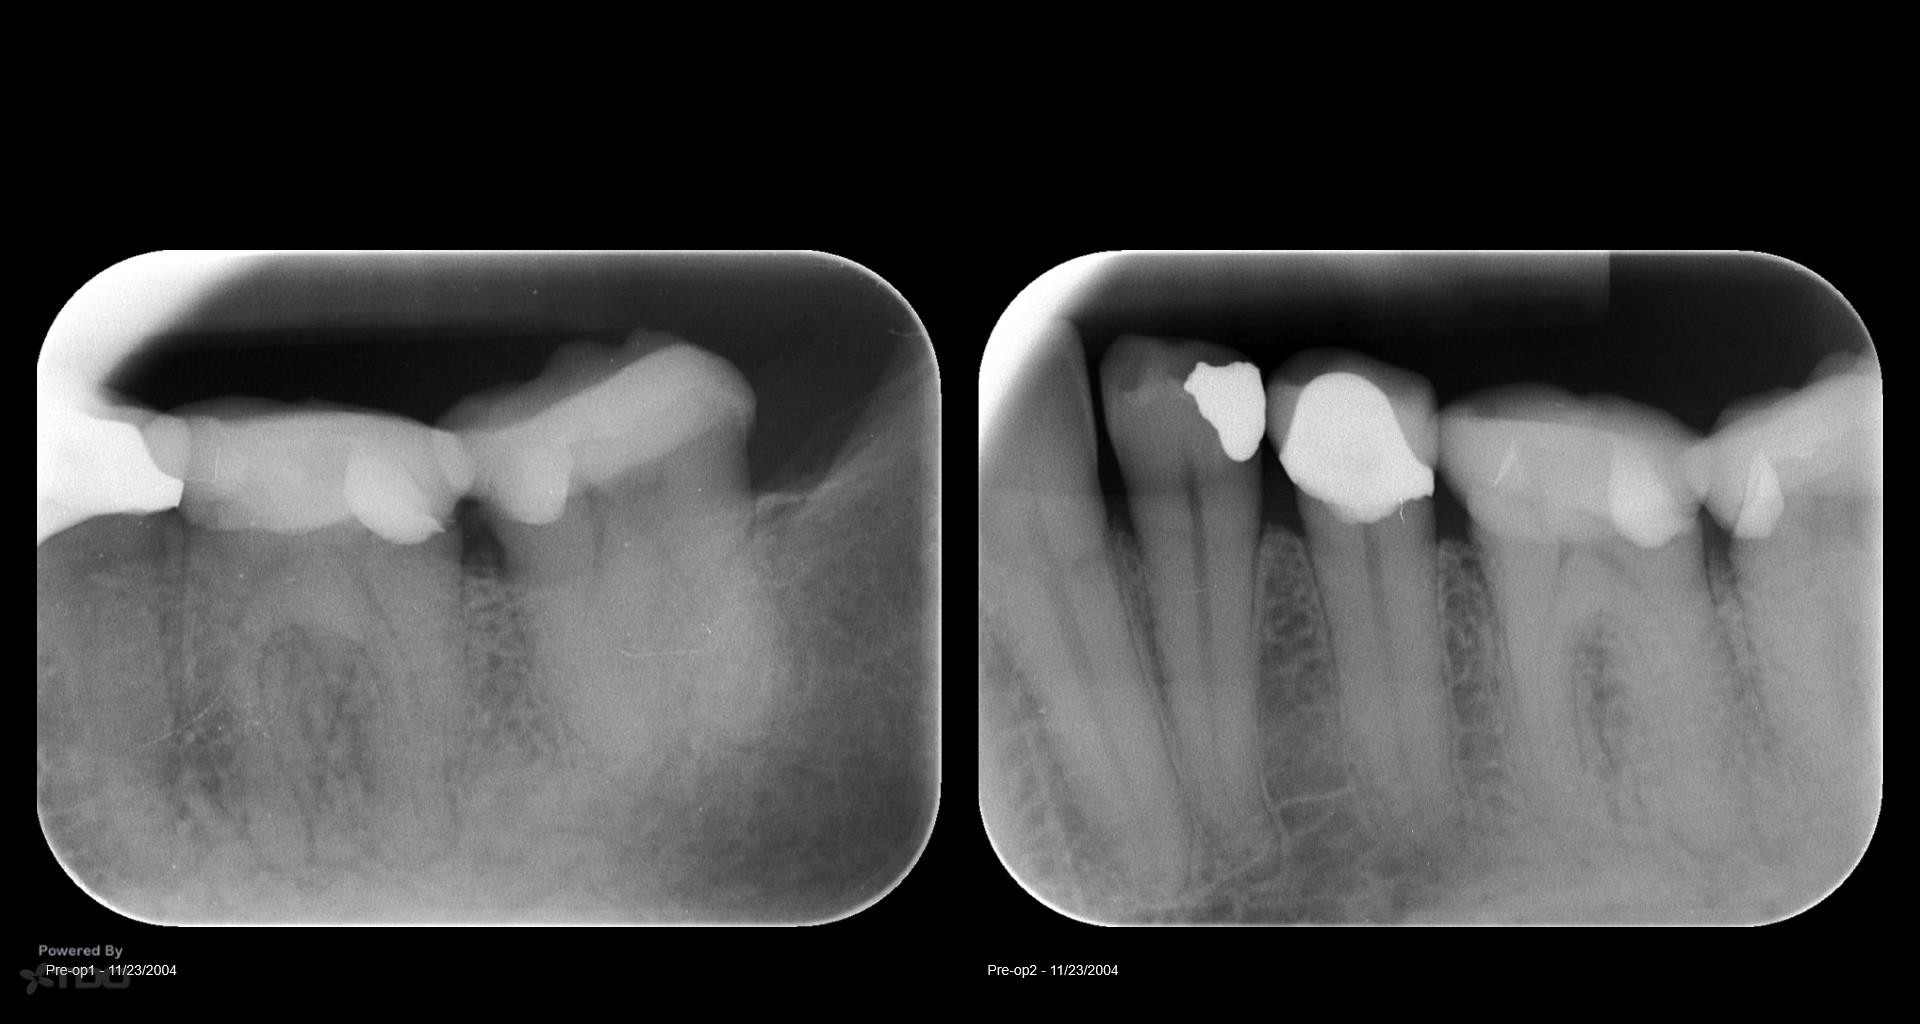

Disappointing recall

Busy recalling cases from the 10-15 yr time frame. Had I just done 5 yr recall, I’d never know …. gbc